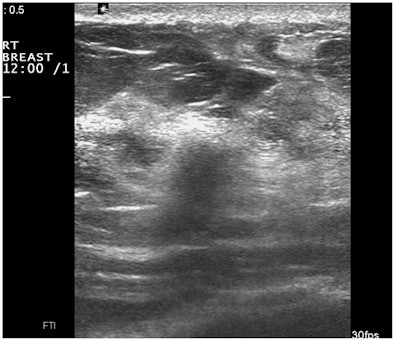

Real-time compound scanning combines the echoes obtained from multiple lines of sight at various angles of ultrasound exposure, compared with the single vertical beam in a standard linear-array transducer, in an attempt to improve the visibility of lesions. But is this technique necessary?

"Due to marketing efforts by some manufacturers, this type of image processing is now a default setting on most scanners sold in this country," Fornage said. "But evidence-based studies proving the superiority of this technique over standard sonography in the detection or characterization of breast lesions are still missing. In fact, the majority of breast ultrasound studies brought in from outside MD Anderson by patients referred to our institution have been performed with real-time spatial compounding and are at times useless because of the blurring affecting them."

Another drawback to this type of image processing is the disappearance of "good" artifacts, such as sound-through transmission, shadowing, and comet-tail artifacts, according to Fornage.

| Images show deterioration with the use of spatial compounding. Above, sonogram of a small carcinoma obtained with spatial compounding turned on. Below, sonogram of the same lesion obtained with conventional grayscale US settings without spatial compounding. |